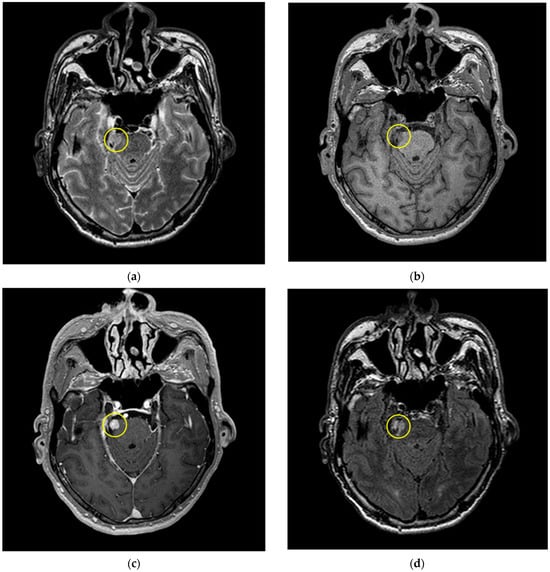

2.1. MRI Dataset

2.2. Image Pre-Processing

3.1. Image Pre-Processing